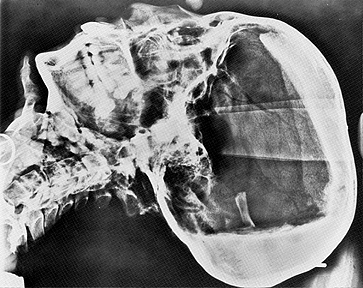

La radiografia del cranio del 1968. I due diversi strati di resina visibili sotto la calotta cranica, in alto, ed a destra nella zona occipitale sono indicati dalle frecce nere. Vicino a quest’ultima, il frammento d’osso che ha generato le ipotesi di assassinio del re (freccia dritta bianca). La freccia curva bianca indica il possibile secondo percorso di estrazione del cervello attraverso il forame magno

Ma – altra anomalia – la sostanza resinosa si era solidificata nel cranio in DUE posizioni differenti, una prima mentre il corpo era disteso ed una seconda con la testa rivolta verso il basso, in posizione capovolta. Probabilmente una seconda operazione di asportazione del cervello è stata effettuata dal forame magno posteriore, non si capisce perché in posizione capovolta.